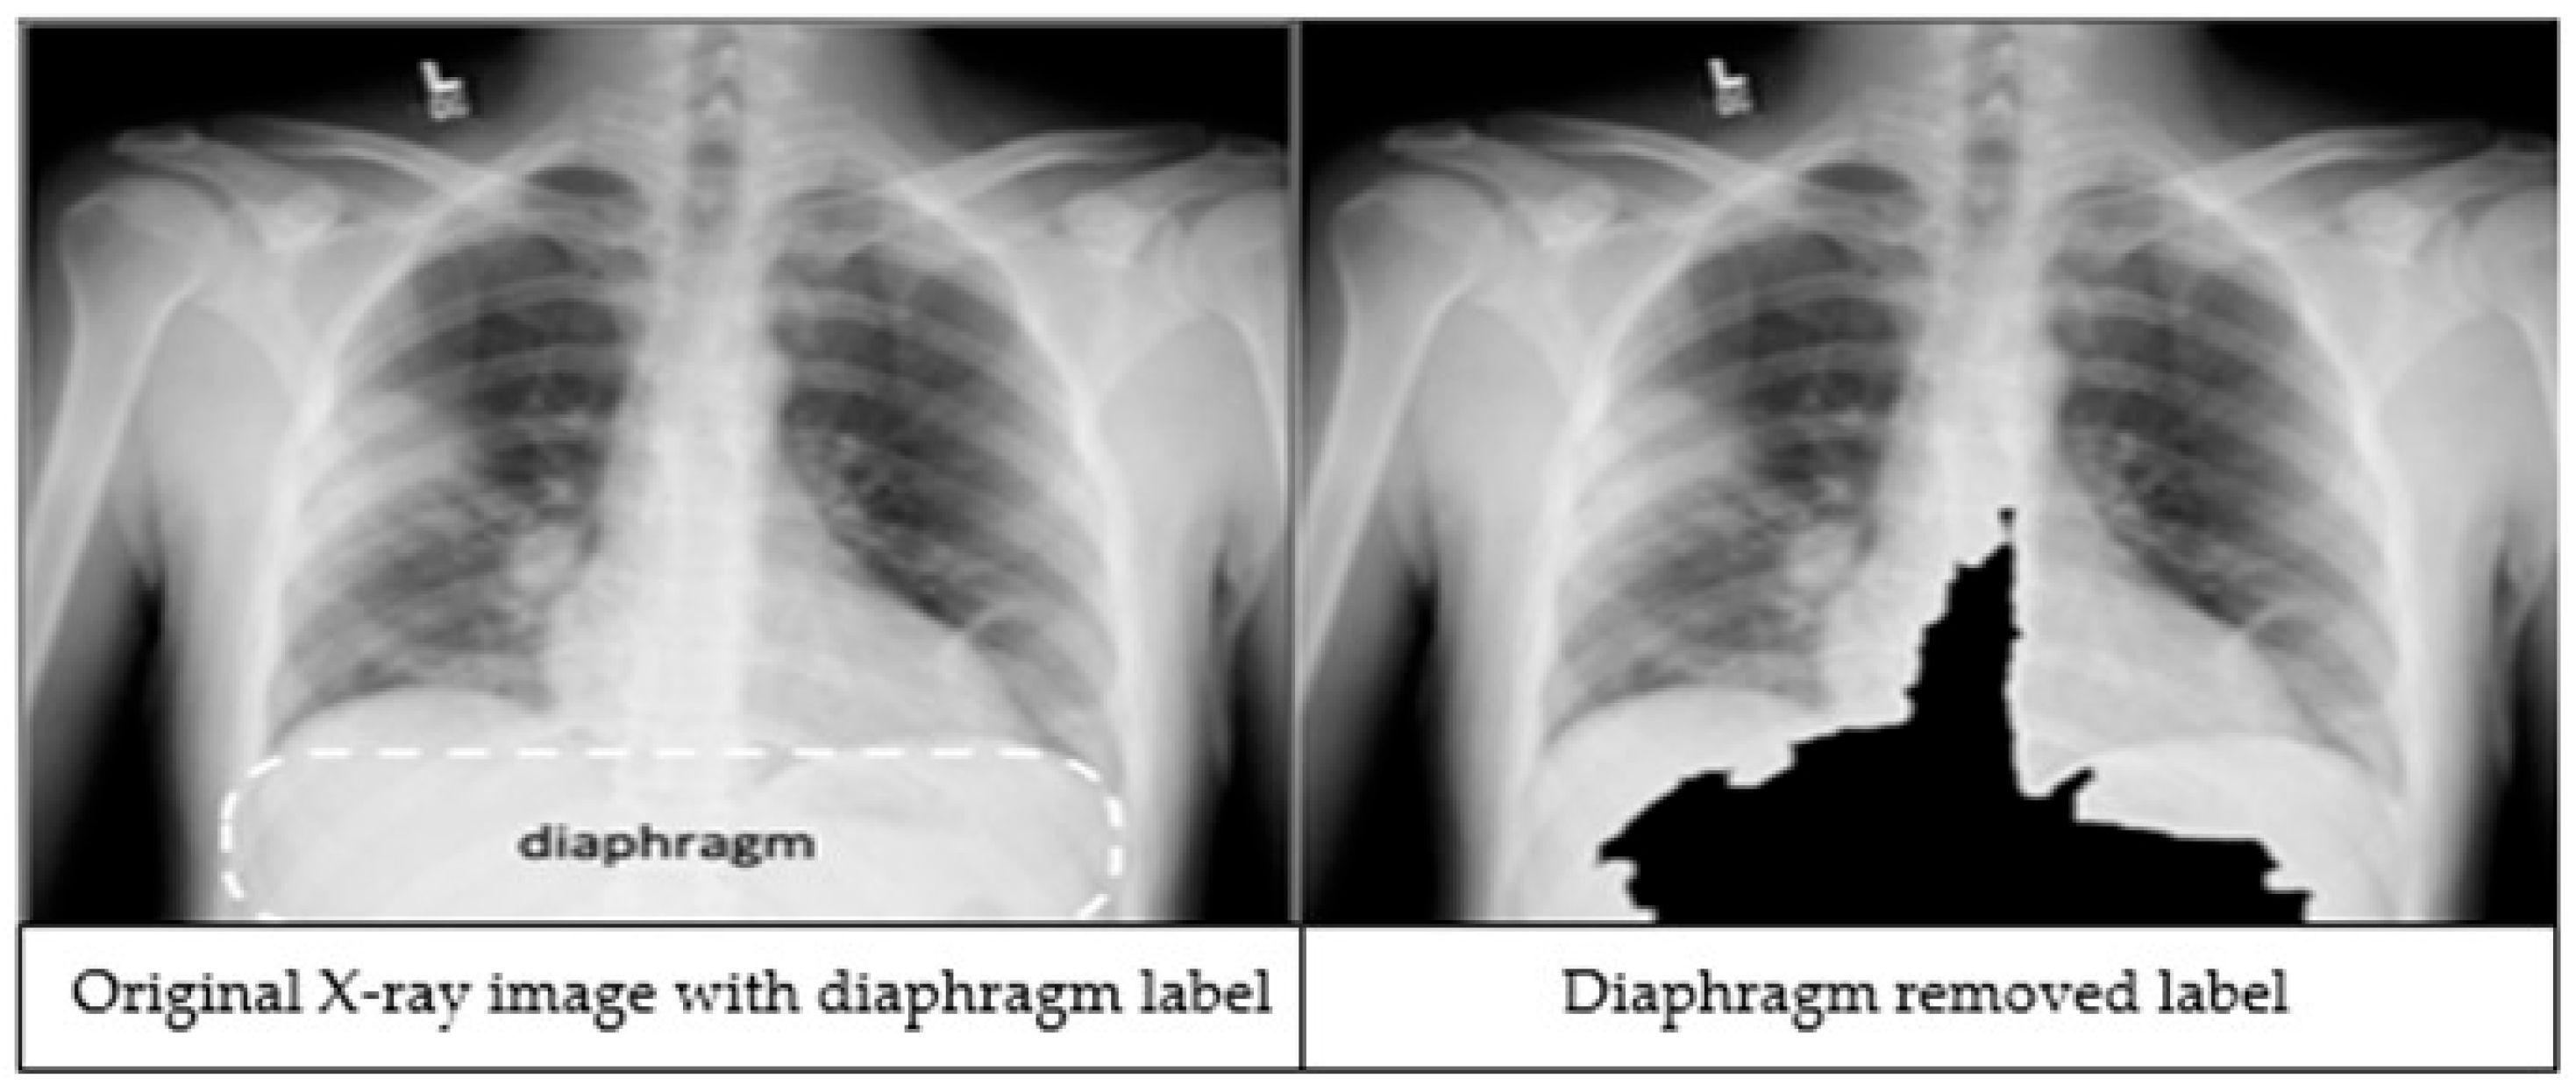

- Additionally, a preprocessing step is employed to remove the diaphragm region in the chest X-ray—often a source of noise for deep learning models—enhancing both accuracy and training efficiency. Beyond chest X-ray abnormality detection, RadAI shows promise for broader applications in medical imaging tasks.

The third preprocessing technique focuses on improving classification accuracy by removing the diaphragm region (see Figure 2) from the X-ray images. The process begins by identifying the maximum and minimum pixel intensities, namely imax and imin respectively. A binary threshold t = imin + 0.9 * (imax − imin) is then applied to convert the image into a binary segmented image. Afterwards, a morphological closing is applied on the binary segmented image to make it a refined mask. Finally, a bitwise operation is performed using the mask image to remove the diaphragm area from the original image, resulting in an image which is called Id.

Figure 2.

An X-ray image showing the diaphragm region of the image within the dashed lines (left). The image after applying the diaphragm removal technique (right).

We applied image preprocessing techniques to automatically detect and remove the diaphragm region from chest X-ray images. Comparative analysis revealed that excluding the diaphragm significantly improved classification accuracy, increasing from 92.69% to 97.29%. While deep learning models are typically capable of learning relevant features without explicit segmentation, our findings demonstrate that removing irrelevant regions through preprocessing can enhance both the performance and robustness of the models.